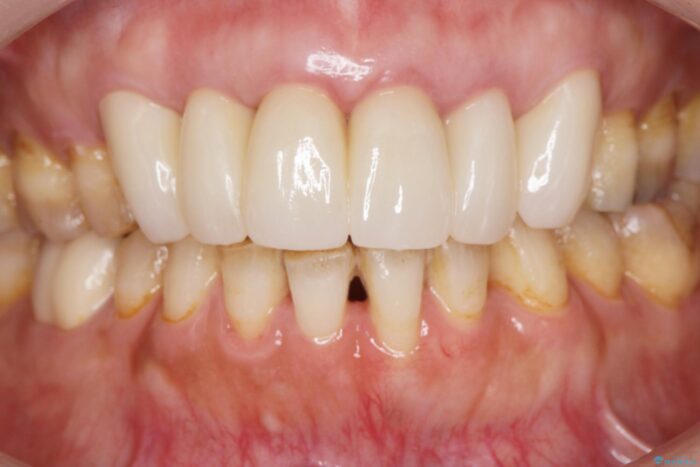

以前に他院で行ったセラミック治療後に、慢性的に歯ぐきからの出血や疼き、違和感がありご相談にいらっしゃった患者様です。

装着されていたセラミックを除去したところ、歯ぐきの奥深くまで歯牙は削られ、歯ぐきの炎症・出血が著しくみられる状態でした。

治療には歯肉を成熟させる期間を含めて約8ヶ月間要しましたが、出血や違和感のない歯ぐきとなり大変ご満足いただけました。